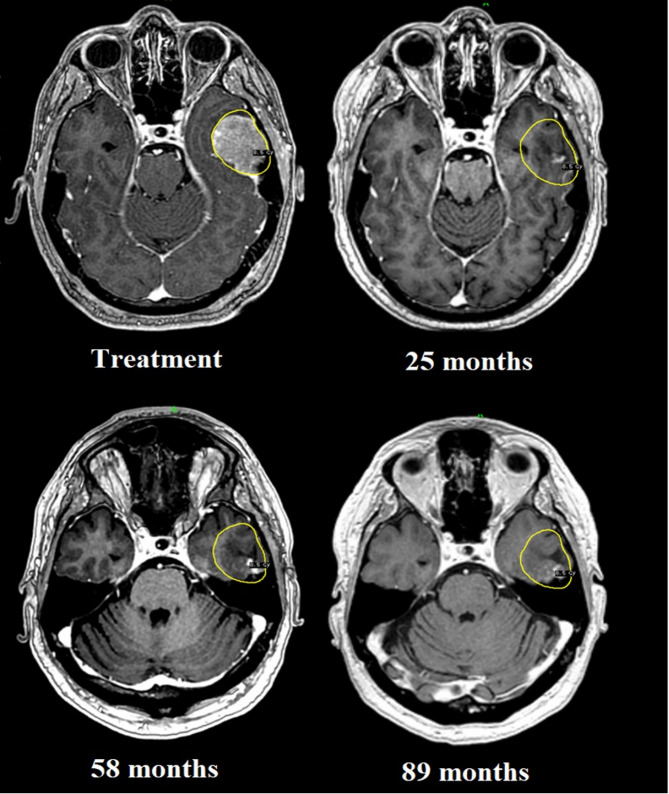

Methods: 29 patients with 35 brain metastases deemed not to be candidates for surgery, radiotherapy or systemic treatment were treated with MRI-guided adaptive Gamma Knife radiosurgery in 3 separate sessions with a 72-hour interval. Customised synchronous double-dose prescriptions were systematically utilised at each session. Estimated survival at pre-treatment was fewer than 4 weeks due to the targeted intracranial lesions. A retrospective analysis was conducted on the whole cohort, with particular emphasis on those surviving 12 months and beyond.

Results: The median overall survival was 7.3 months, with a follow-up of 7.5 years. Survival at 6, 12, 24, 36, 48 and 60 months was 62%, 41%, 17%, 14%, 10% and 7%, respectively. Local tumour control (LTC) at 1 year was 75%. 4 patients developed local recurrence late on follow-up, with a survival ranging between 12 and 40 months. 2 patients were alive at the time of submission (115- and 117-months post-treatment) with no sequelae; the remainder succumbed to general disease progression, with neurologic death being avoided throughout the whole cohort. Adverse radiation effects (ARE) were reported in 5 patients, of which 4 remained asymptomatic throughout follow-up.